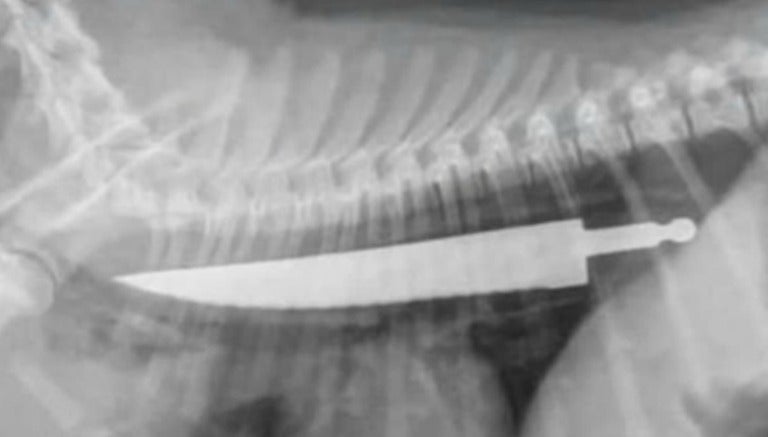

El cachorro de nombre Lexy se comió el artefacto sin morderlo, ni doblarlo, y fue hasta que se le hicieron estudios Rayos X que se dieron cuenta del caso.

La médico veterinario Jody Braddock aseguró que nunca había visto algo igual, esto después de extraerle el cuchillo con sumo cuidado para no cortar por dentro al perro de raza Bull-terrier.